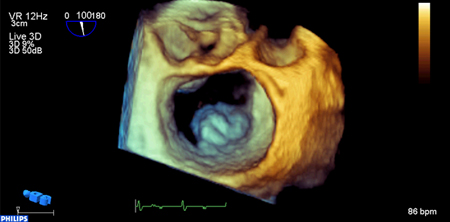

Mitral valve P2 leaflet prolapse: 3D view

From the collection of Prakash P. Punjabi